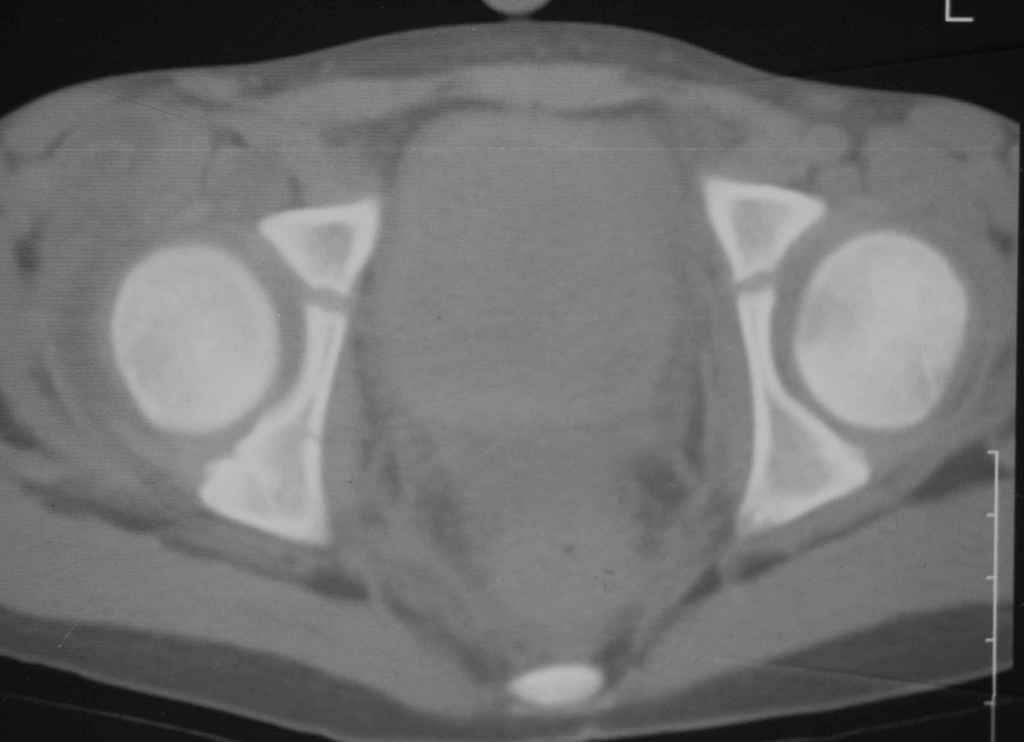

Уважаемые коллеги, помогите определиться с тактикой лечения.Ребёнок 7 лет, травма 11.09.08, поступил с травматическим вывихом бедренной кости.

Вывих вправлен, конечность фиксирована на скелетном вытяжении. Что делать с переломом подвздошной кости? Лечить консерватино или оперировать?